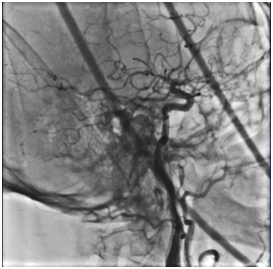

Выполнено контрольное дуплексное сканирование брахиоцефальных артерий, по результатам которого выявлен 80% стеноз устья правой внутренней сонной артерии (пВСА). Пиковая скорость кровотока в пВСА – 250 см/сек. Учитывая рецидивирующую клинику ТИА, гемодинамически-значимое поражение правой ВСА – больному рекомендована реваскуляризация в бассейне правой ВСА. Однако при селективной ангиографии брахиоцефальных артерий выявлена короткая окклюзия правой ВСА от устья.

Интракраниальные отделы кровоснабжаются из бассейна левой сонной артерии по Вилизиеву кругу.

Учитывая «симптомность» поражения сонной артерии, а также благоприятные анатомо-морфологические характеристики поражения и высокую вероятность успеха эноваскулярного лечения - принято решение о проведении ангиопластики со стентированием правой внутренней сонной артерии с использованием проксимальной системы защиты головного мозга.

Выполнена аспирация 60 мл крови через систему церебральной протекции с получением атеросклеротического дебриса до получения «чистой» крови. Поочередно произведено снижение давления в дистальном и проксимальном баллонах системы, антеградный кровоток по правой ВСА восстановлен. Интракраниальные отделы хорошо кровоснабжаются из бассейна правой сонной артерии.